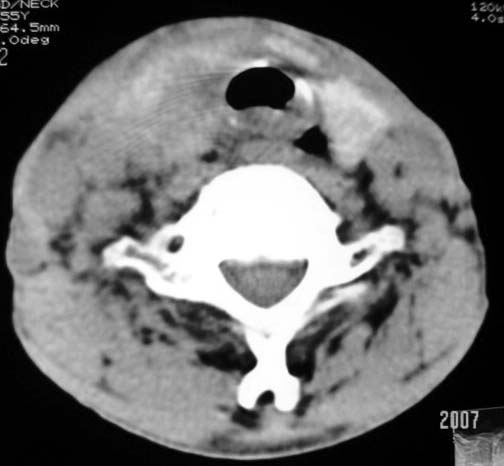

以下是引用dyqct在2007-4-20 16:19:00的发言:[br]考虑:1、左侧梨状窝区破裂伴左颈深、浅部气肿。[br] 2、右侧甲状腺区血肿(请追问病史是否伤及右颈部)。[br] 3、建议病情稳定后增强扫描除外右侧甲状腺腺瘤。